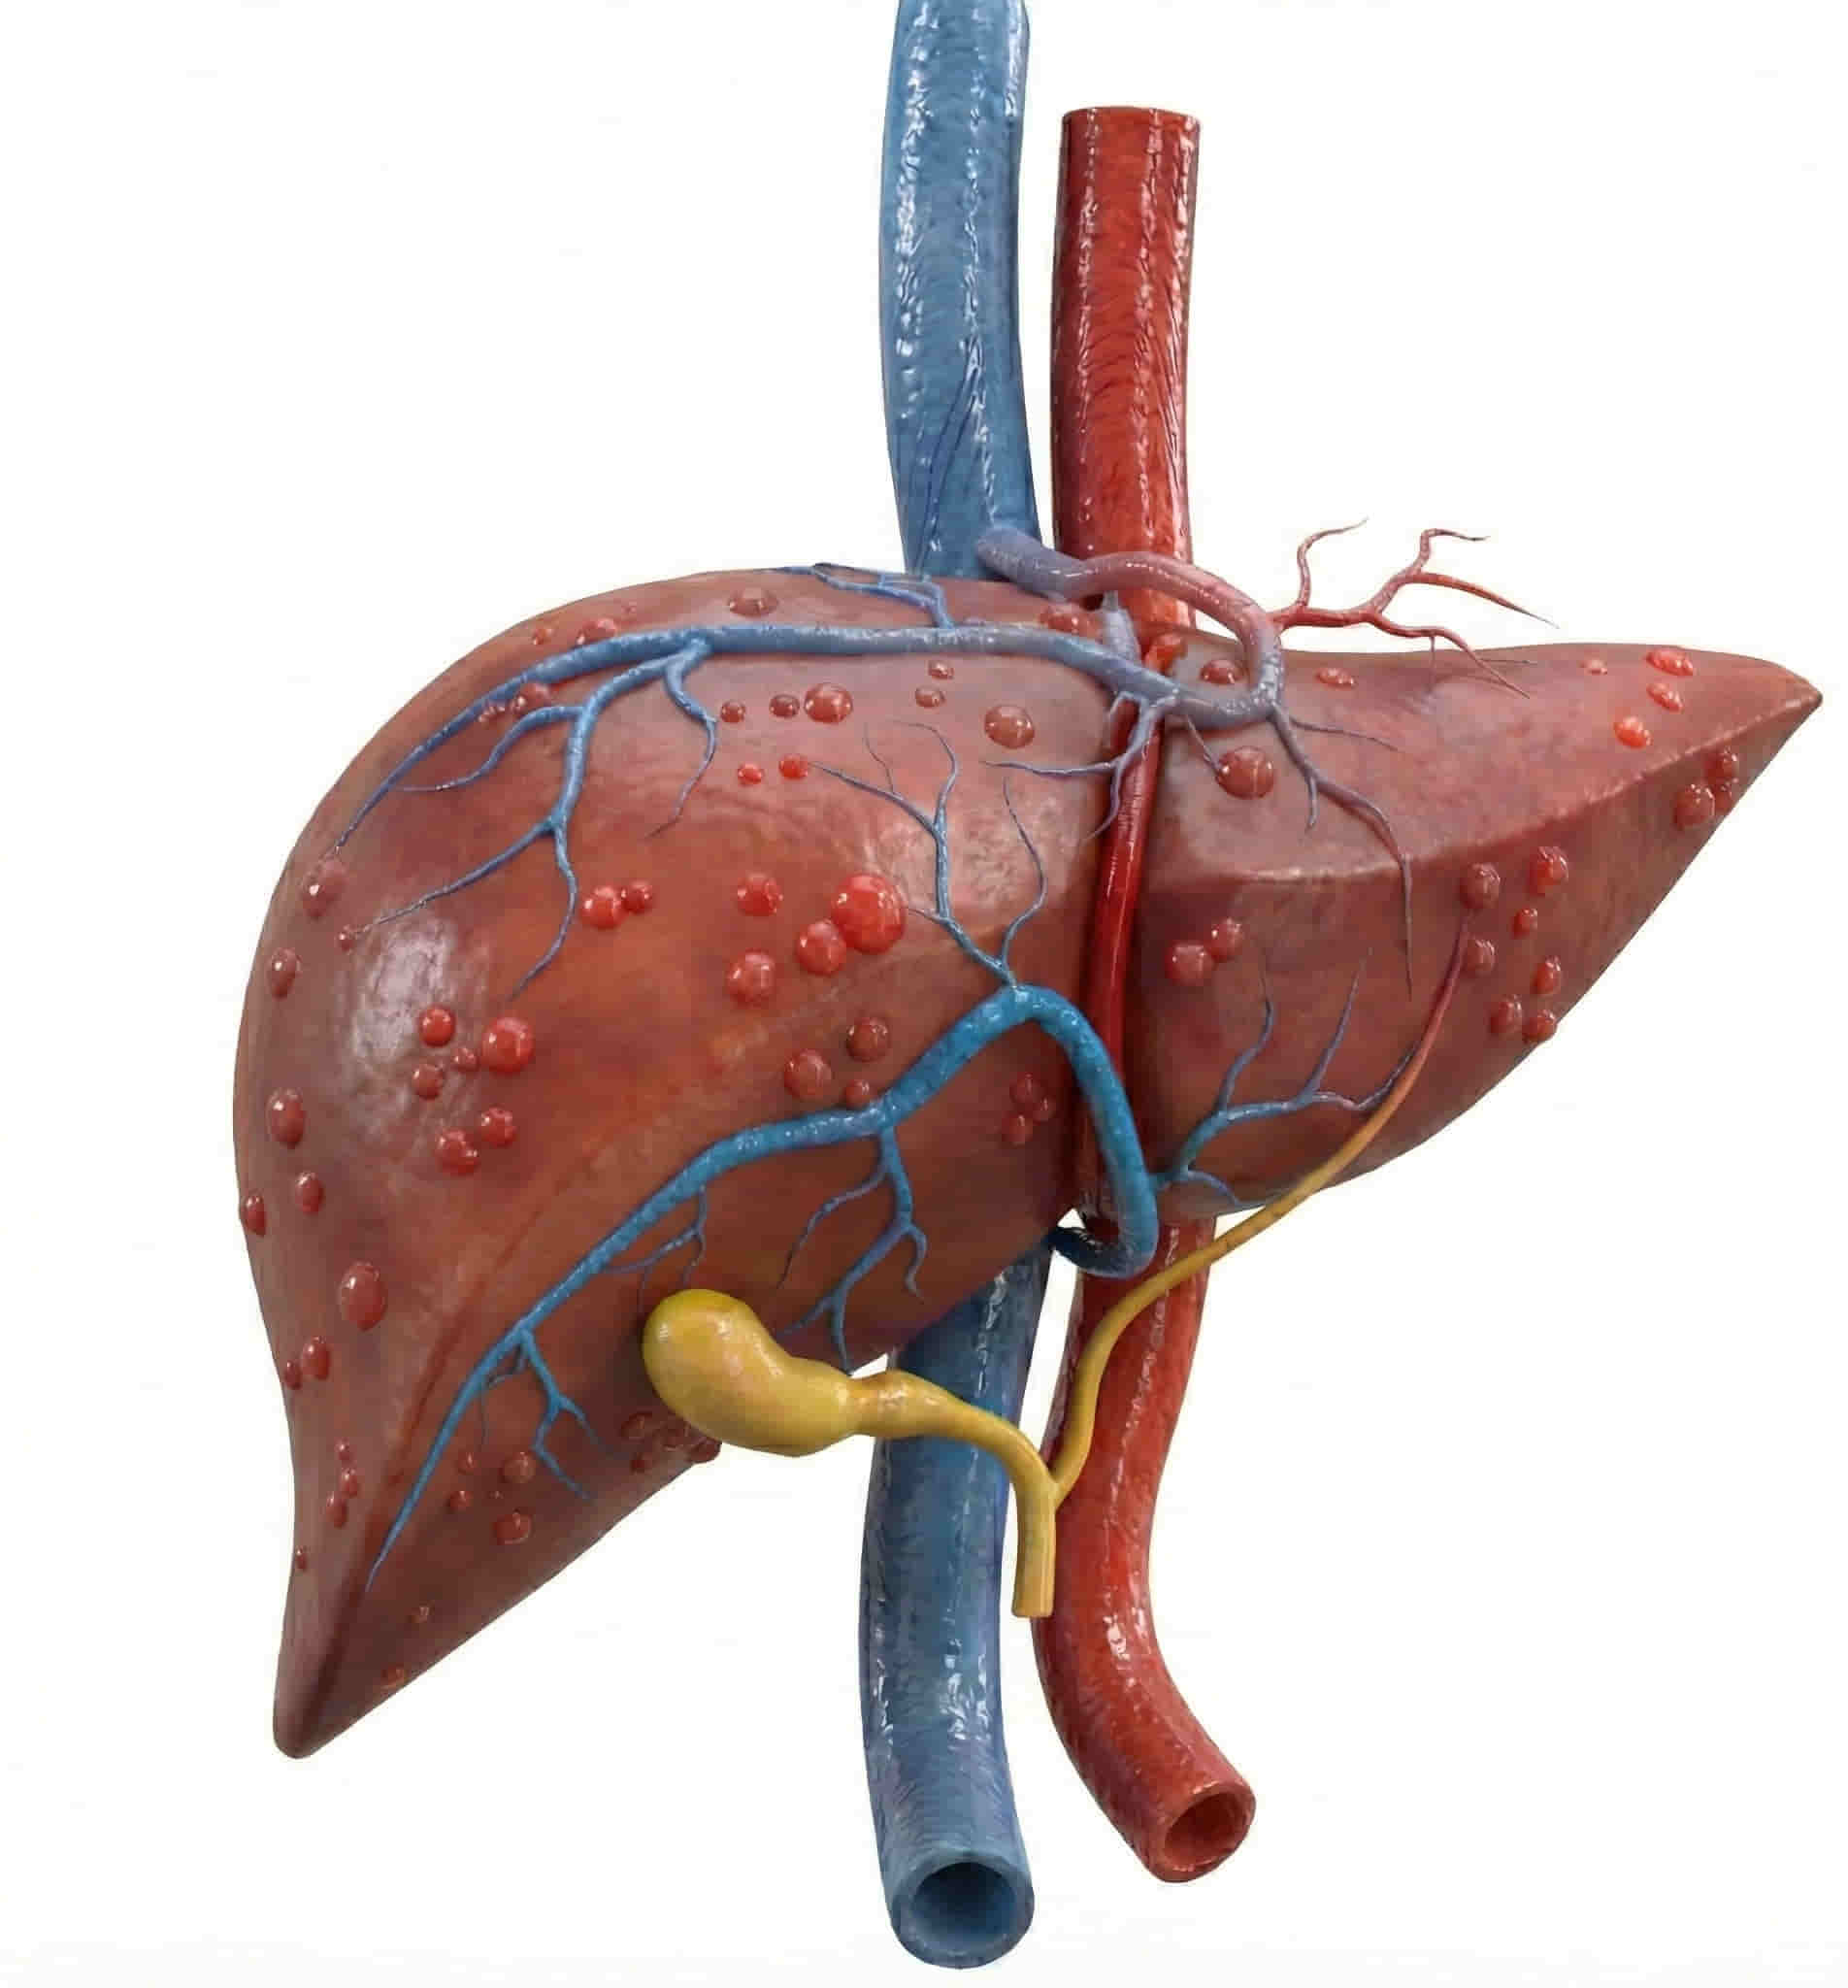

🩺 What is a Transhepatic Venous Catheter?

This procedure involves placing a catheter directly through the liver and into one of the hepatic veins, which then drains into the Inferior Vena Cava (the body’s largest vein). Because of the complexity of the anatomy, this “extreme access” procedure is only performed by the most experienced interventional radiologists in India.

The liver is a large, resilient organ. The catheter occupies a very tiny path through the liver tissue, which does not affect your overall liver function. The site heals quickly around the catheter.